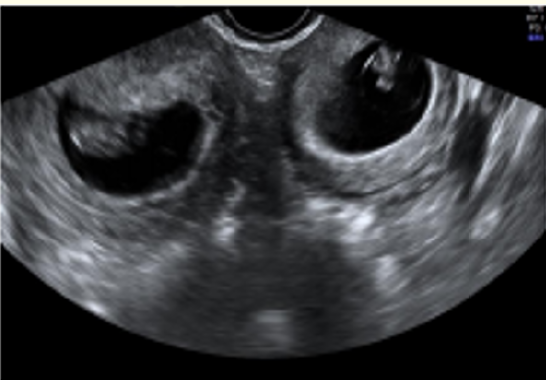

A Rare Case of a Twin Pregnancy in a 27 Year Old Patient with Uterus Didelphys

N Usman, Nageen Naseer, S Anwar, R Sallam and T Hayes. 12(2): 26-30.